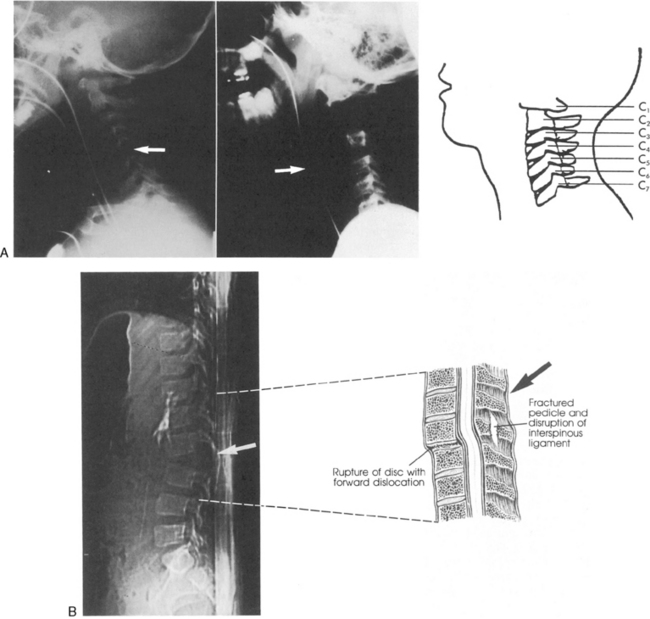

The cervical spine is relatively unstable and is still developing in young children. As a result, SCI patterns in children differ from those in adults. The ligaments along the child's cervical vertebrae are relatively lax, and the paraspinous muscles are incompletely developed. The child's vertebral bodies are wedge-shaped and not completely ossified. In addition, the facet joints of the cervical vertebrae are relatively flat. For these reasons, the vertebrae can shift several centimeters during injury or the application of force to the spine, resulting in spinal cord injury without evidence of injury to the vertebrae. Although the pediatric spine is relatively more elastic than the adult spine, it will be injured if significant cervical subluxation occurs (Fig. 11-19).

image image

Fig. 11-19 Spinal cord injury. Many injuries resulting in spinal cord damage produce visible radiographic changes, although a significant number (20%-60%) are not associated with any skeletal fracture or dislocation. A, Lateral cervical spine radiographs demonstrating skeletal abnormalities associated with cervical spine injury. The first radiograph is from a 4 year old who was restrained in a car seat that was not anchored in the car. The separation between the fifth and sixth cervical vertebrae is subtle but detectable (arrow), especially when compared with the line drawing of normal anatomy (far right). Radiopaque orogastric and nasogastric tubes are visible; they are slightly displaced anteriorly, indicating a small amount of edema surrounding the spinal cord injury. The location of the injury is unusual for this age. The second radiograph shows a 5-year-old pedestrian struck by an automobile and demonstrates significant separation between the first and second cervical vertebrae. This is a more common site of cervical spine injury in young children. Note the anterior displacement of the nasogastric tube (arrow) produced by edema surrounding the injury. An endotracheal tube is present but not visible. The line drawing depicts normal cervical spinal anatomy in a 3- to 4-year-old child. B, This scan film performed before a computed tomography scan demonstrates lumbar vertebral and spinal cord trauma associated with a lap belt injury. Separation of the lumbar vertebrae can be seen (arrow) and resulted in paraplegia. This injury resulted from flexion of the lumbar spine (see drawing). C, Flexion injury of the lower thoracic vertebrae and spine is visible on this anteroposterior chest radiograph. This radiograph shows an unrestrained 16-year-old driver who was thrown from the car. The lateral flexion resulted in compression of the spinal cord and fracture of the thoracic vertebrae (see arrow and corresponding illustration). The rod placed during surgery is visible. D, This magnetic resonance imagery scan shows in detail the skeletal and spinal damage resulting from a flexion-rotation injury. This 16-year-old motorcycle driver sustained displacement of two vertebrae (white arrows) and fracture of two vertebrae and one disc. Resulting compression of the cervical spine produced a complete spinal cord injury. A contusion is visible in the spinal cord (black arrow). The line drawing depicts the injury.

(A, courtesy Carol Gilbert and John Feldenzer, Roanoke, Va. Drawing reproduced from Riviello JJ, et al: Delayed cervical central cord syndrome after trivial trauma, Pediatr Emerg Care 6:116, 1990. B, courtesy Bennett Blumenkopf, Vanderbilt University Medical Center, Nashville, Tenn. Line drawing reproduced from Rudy EB: Advanced neurological and neurosurgical nursing, St Louis, 1984, Mosby. C, courtesy Noel Tulipan, Vanderbilt University Medical Center, Nashville, Tenn. Illustration reproduced from Rudy EB: Advanced neurological and neurosurgical nursing, St Louis, 1984, Mosby. D, courtesy Bennett Blumenkopf, Vanderbilt University, Nashville, Tenn. Line drawing reproduced from Rudy EB: Advanced neurological and neurosurgical nursing, St Louis, 1984, Mosby.)